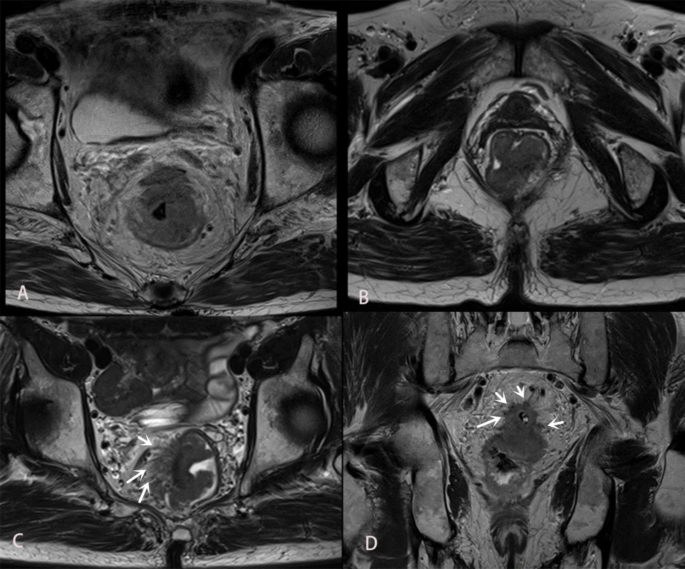

Based on Smith’s 5-point rating system12, mEMVI negative was diagnosed with a score of 0 to 2, while mEMVI positive was determined with a score of 3 to 4. Pelvic nodules that showed high signal on high b-value DWI were classified as mLN13 if they met either of the following two criteria on HRT2WI: (i) nodules with a short diameter greater than or equal to 1.0 cm; (ii) nodules with a short diameter less than 1 cm exhibited significant internal signal heterogeneity, rough or lobulated margins. Primary lesions of rectal cancer could grow in two distinct patterns: annular infiltration, where the tumor extended in a circular or semi-circular manner along the rectal wall (Fig. 2A), and localized mass growth, characterized by a round or oval shape. When the primary lesion was confined within a limited area and had an irregular shape, but its maximum width was greater than half of its length, it was also considered as localized mass (Fig. 2B and C). Referring to the histopathological concept of TBC14, we classified the MRI tumor border morphology into iTBC and pushing TBC (pTBC). iTBC was characterized by multiple nodules or cords of varying sizes at the margin of the primary tumor, exhibiting irregular and rough boundaries (Fig. 2C and D). On the other hand, pTBC was characterized by clear boundaries of the primary tumor or the presence of a single smoothly-bordered nodular protrusion, or uniformly thick and well-defined cords at the tumor margin (Fig. 2B).

A: The primary lesion of rectal cancer demonstrates circumferential wall infiltration. B: A morphologically irregular, lobulated, focal soft tissue mass is observed in the left posterior wall of the rectum. The mass predominantly protrudes into the lumen, with clear lesion boundaries. It is categorized as a localized mass and pTBC. C: An irregular mass is observed in the right wall of the rectum, with multiple uneven and rough border indistinctive strands (white arrow) seen on its right edge. The growth pattern is classified as localized mass and iTBC. D: Axial HRT2WI shows multiple small nodular projections (white arrow) along the edge of a round-shaped primary cancer lesion. These nodules exhibit rough margins, and irregular small strands are observed near the margins. It is classified as iTBC.